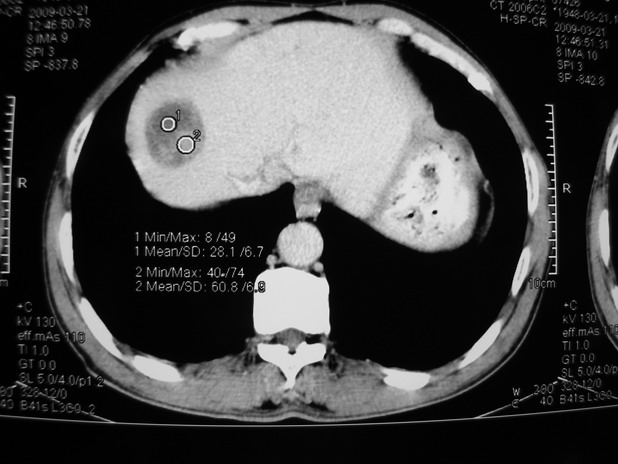

以下是引用余辉在2009-3-21 21:36:00的发言:[br]图像太乱了,建议楼主直接将强化数据按顺序列出来,病灶位置较表浅薄,有肝炎病史,灶内实性成分有显著强化,动脉期约60hu,考虑肝癌可能性大,进一步检查。